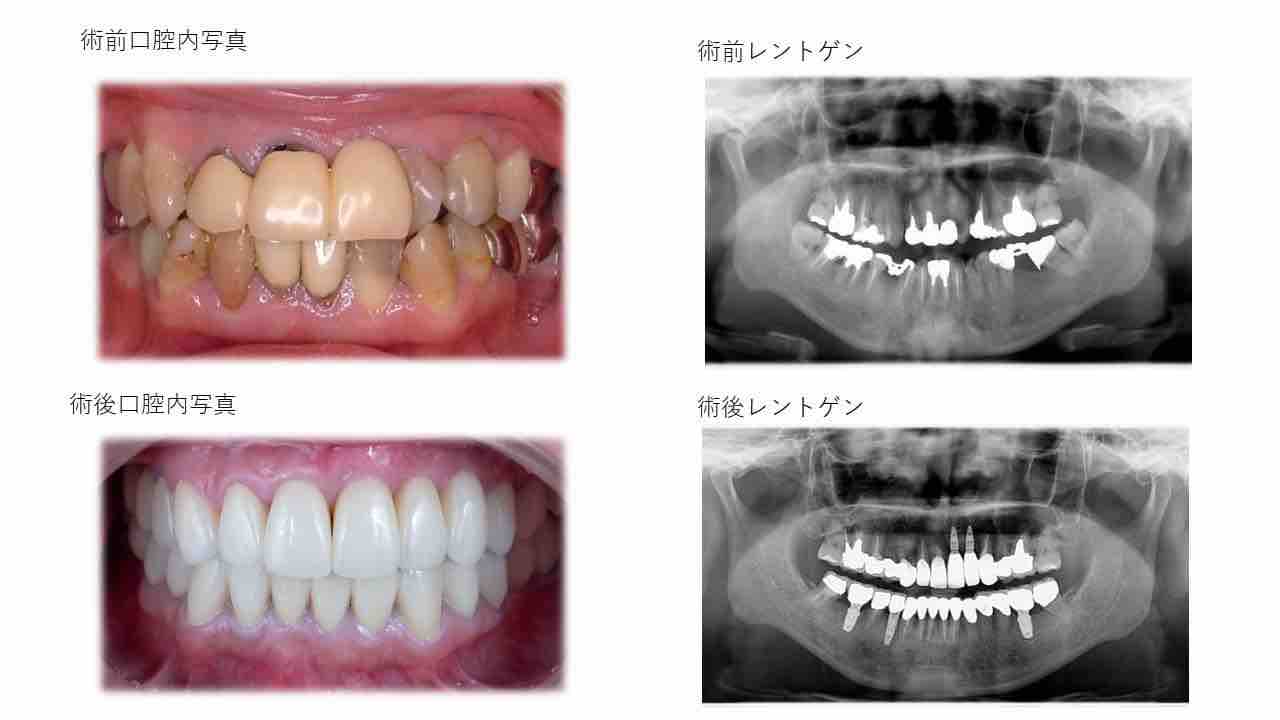

¥¤¥ó¥¹¥¿¥°¥é¥à¤ËºÜ¤»¤Æ¤¤¤ëÅö±¡¤Î¾ÉÎã¤Ç¤¹

ðÌî»õ²Ê¾ÉÎ㢠ÀèÅ··ç»¶ºÀµ¥¤¥ó¥×¥é¥ó¥È

ðÌî»õ²Ê¾ÉÎã¡¶ºÀµ¥¤¥ó¥×¥é¥ó¥È¥»¥é¥ß¥Ã¥¯